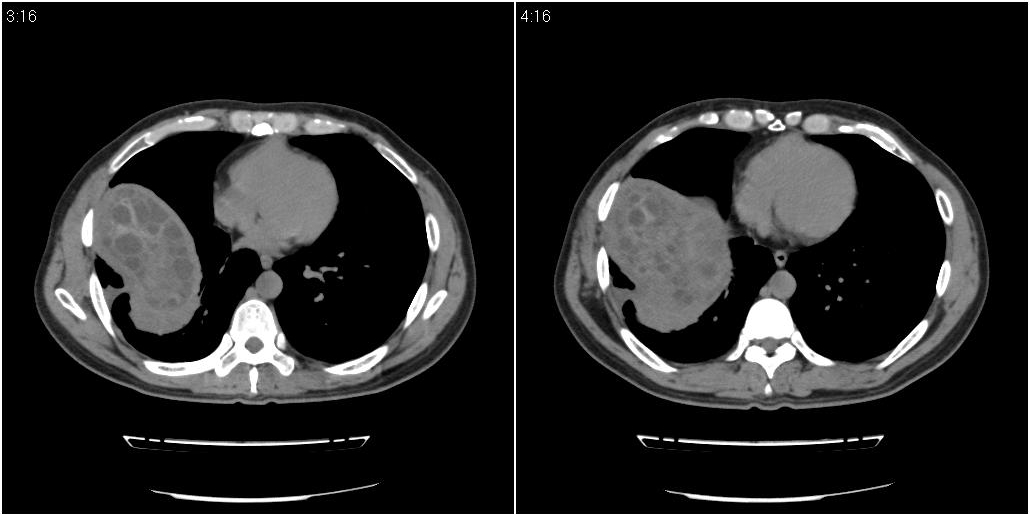

该患者70岁男性,手术后10年,现复查。2008年6月份本人曾经发过一极其类似的病例,只是部位略有差异。

肝脏多房性包虫囊肿

水上浮莲征,肝包虫囊肿。

肝脏及右侧胸腔包虫病。

大囊套小囊!肝脏多房性包虫囊肿